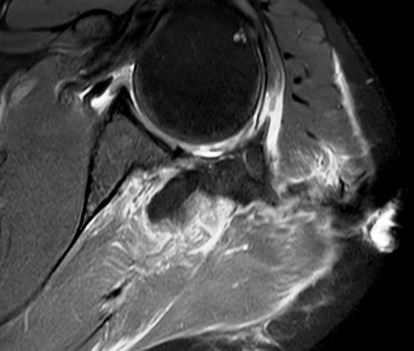

Figure 3 for case Stab wound

Figure 3

Discussion

Filled with hemorrhage. The infraspinatus took the brunt.